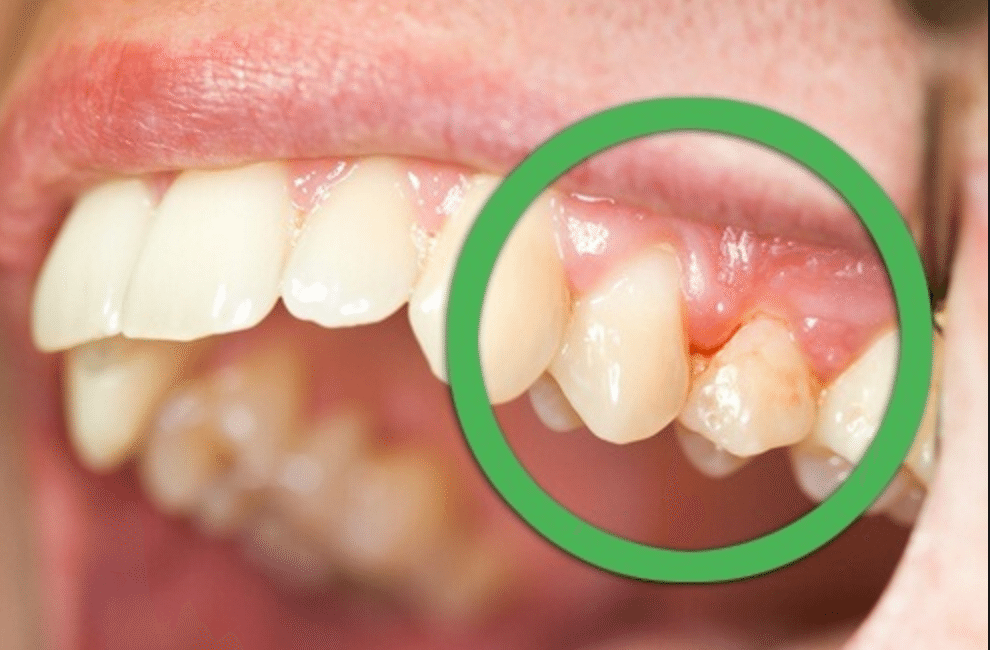

Quando a gengivite se agrava, ela pode causar o que chamamos de “gengivite expulsiva”. Isso significa que a gengiva começa a se afastar dos dentes, criando espaços onde sujeira e bactérias se acumulam ainda mais. Imagina só, os dentes parecem mais longos e até a sensibilidade pode aumentar. É um sinal claro de que a saúde bucal precisa de atenção urgente.

Essa tal de gengivite, quando começa a dar trabalho e a gengiva parece que se afasta do dente, pode ser um sinal de que algo não vai bem. Na maioria das vezes, a causa é a má higienização, sabe? Aquela placa bacteriana que a gente não tira direito e que vai irritando tudo. Com o tempo, essa inflamação pode ir “expulsando” a gengiva, deixando a raiz do dente exposta. Isso não é legal e pode até doer.

Muita gente pensa que gengivite expulsiva é algo que simplesmente some sozinho, mas isso é um mito danado! A gengivite, de modo geral, é uma inflamação que precisa de atenção. Quando ela causa um recuo visível da gengiva, o termo “expulsiva” entra em jogo, indicando que algo está “expulsando” ou afastando o tecido gengival. Não é algo para se ignorar, viu?

E quanto a tratamentos milagrosos? Pois é, outro ponto que gera muita confusão. Não existe uma única fórmula mágica que sirva para todo mundo. O tratamento da gengivite expulsiva depende muito da causa. Pode ser desde uma escovação muito agressiva até questões mais complexas. Por isso, o ideal é sempre procurar um dentista. Ele vai saber diagnosticar o motivo e indicar o melhor caminho para você.